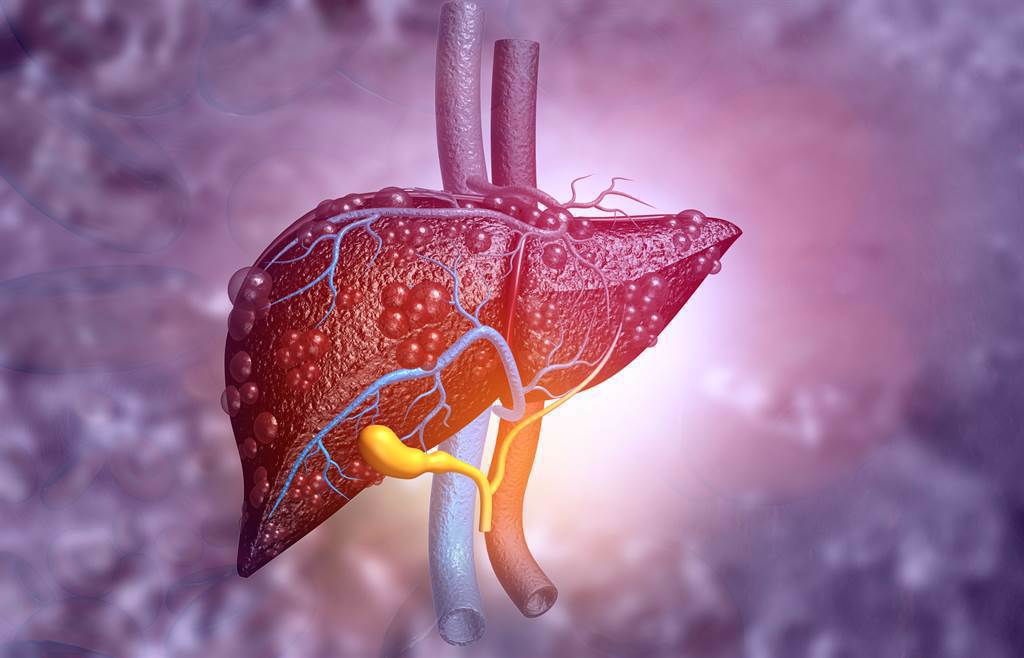

大腸癌初期症狀往往不明顯,千萬別因害怕檢查錯失治療良機!急診專科醫師貝琪梨日前分享令人惋惜的案例,一名48歲男子因一天連解3次血便前來求助,經檢查確診為大腸腺癌,最終手術切除右半側大腸。醫師透露,男子曾因覺得大腸鏡「戳進肛門」的感覺過於可怕,拒絕與母親一同檢查,若當初配合,也許一切都會不一樣。她沉痛呼籲,「預防勝於治療」,再忙也務必定期安排例行健檢。